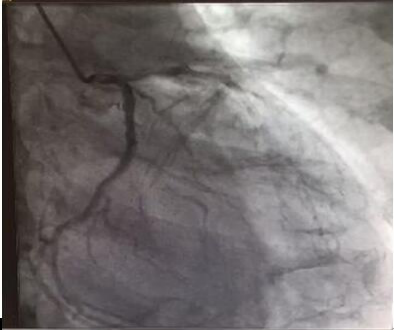

2004年的一天,M先生突然接到家人的电话,父亲胸闷、大汗淋漓且突然晕倒,他紧急赶往医院。虽被诊断为急性心肌梗死,但是目前不用手术,可以用药物来控制。持续服药,他父亲的情况好多了,胸闷气短的症状也得到缓解。2006年,M先生的父亲的病情出现了反复,胸闷气短的症状加重。对父亲的病情,M先生从来不敢马虎,立即去了医院,在医生的安排下做了一系列的检查,果然,父亲的情况加重了,冠脉造影显示严重的三支病变,医生建议手术。在2006年9月,M先生的父亲进行了心脏手术,术中给予前降支置入支架3个,手术后,他父亲的情况得到改善。

国内冠状动脉造影(赴美就医机构爱诺美康提供)